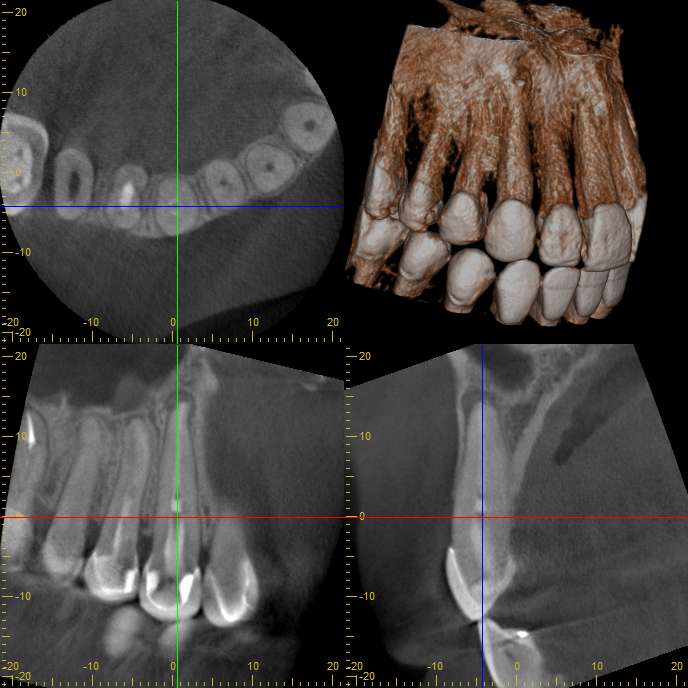

人気記事 2025.08.02 破折(ひび割れ)した前歯に対してインプラント1本を埋入 2026.02.17 「原因不明」と言われた痛み——CTで第2根管を確認し、抜髄で改善したケース 2025.10.14 抜歯宣告を受けた歯を、精密根管治療で保存したケース(右上3番)